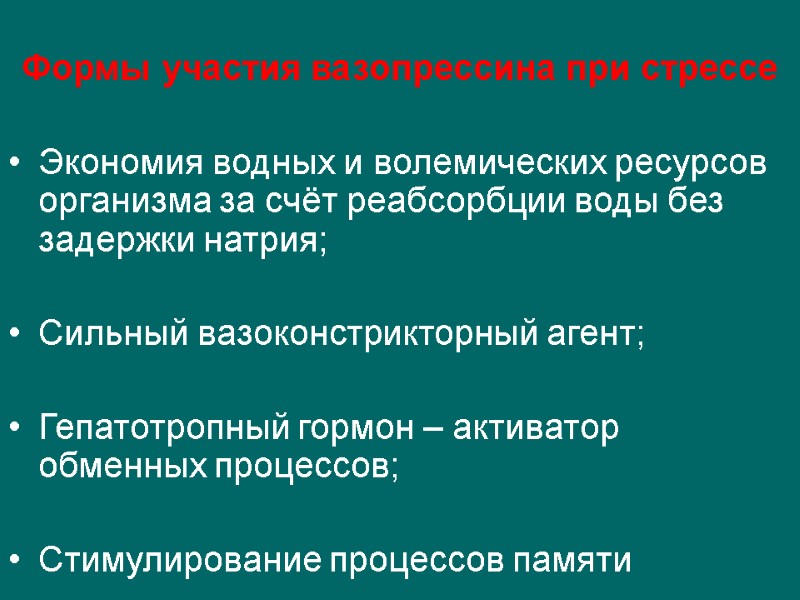

Формы участия вазопрессина при стрессе Экономия водных и волемических ресурсов организма за счёт реабсорбции воды без задержки натрия; Сильный вазоконстрикторный агент; Гепатотропный гормон – активатор обменных процессов; Стимулирование процессов памяти